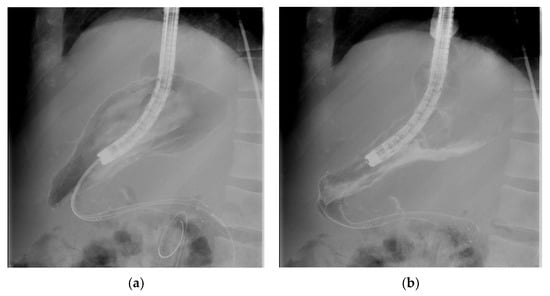

2.5. Esophageal Stents